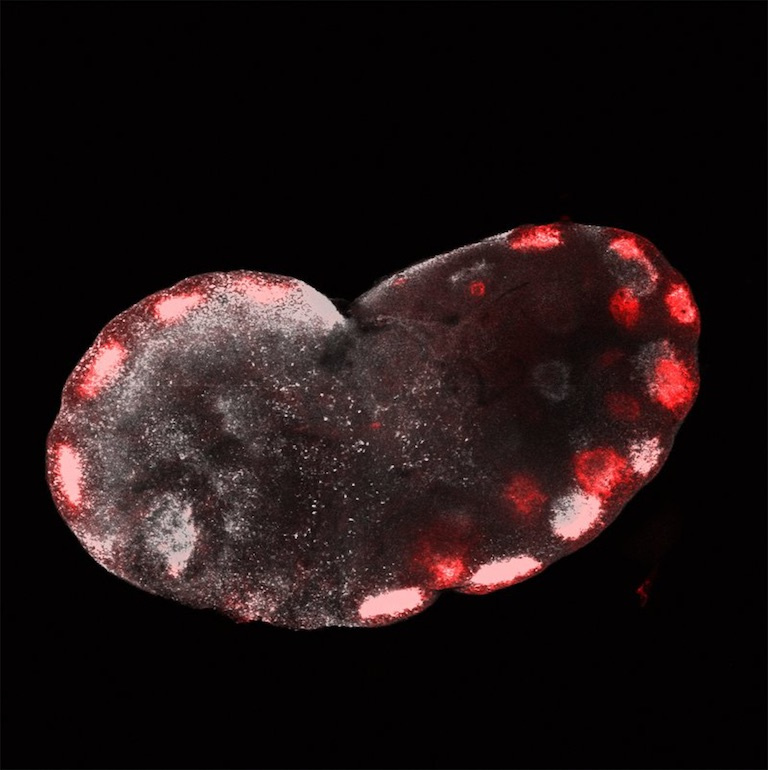

Vaccine targeting to the lymph node, an immune cell rich organ, is critical for vaccine efficacy. The images was taken 7 days after a preventive HIV vaccine was administered to mice via injection and shows vaccine accumulation in the lymph node. The vaccine that has reached the lymph node would interact with (teach) the immune cells to produce strong vaccine specific immune responses necessary to prevent a future infection taking us one step closer to a world without HIV.